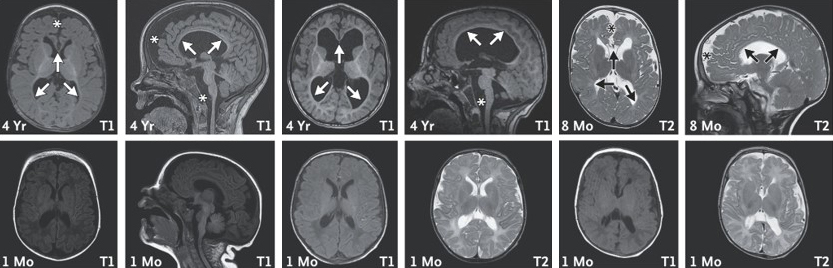

Magnetic resonance imaging (MRI) scans of the brain in three children with a missing copy of the Chaserr gene. The scans performed at age 8 months or 4 years (top row) reveal structural changes in the brain, including reduced volume of the brain stem (asterisks) and decreased myelin coating of nerves (arrows) in deep-seated brain areas. These changes are less apparent at 1 month of age (bottom row)

Lab tests showed that the children’s cells had elevated CHD2 levels, just as the Weizmann researchers had seen in the mouse models. MRI scans revealed that in the first years of the children's lives, there had been progressive damage to white matter in the brain, the tissue responsible for refining and coordinating signals between nerve cells.